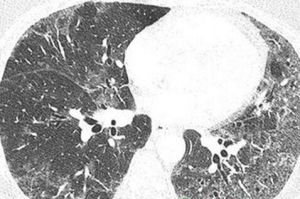

X線胸片有特徵性變化,約75%的病人具有十分相似的肺部陰影,主要表現為一個三角形陰影,自肺門沿心臟向兩肺基底伸展,三角形的底在側面,尖在心膈角處,陰影模糊呈磨玻璃狀自肺門向下放射的紋理明顯增粗,為擴張的肺血管影。陰影在心緣部增濃,肺外圍變淺和減少。這種典型陰影有時可持續4~6年不變,有的則在數月內發生變化或逐漸吸收。25%的病人可表現為瀰漫性模糊的斑點狀肺陰影或除了有肺基底三角形陰影外,同時還有自肺門向上肺野呈放射性線條狀和點片狀模糊陰影。總觀肺野,呈現一種“髒肺”(dirty -lung)面貌。HRCT上有50%~70%呈磨玻璃表現也可有灶性、片狀陰影主要病變分布在下肺和中肺野。50%~60%有不同程度的纖維化,但遠比IPF為輕也很少有蜂窩肺。部分病例出現胸膜下肺大泡,易並發自發性氣胸。支氣管肺泡灌洗液中以淋巴細胞肺泡巨噬細胞和漿細胞為主的炎性改變。